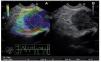

Category 1 is for a homogenous low elastography area (soft, green) and corresponds to the normal pancreas tissue (Figure 1). For images classified as category 2 (Figure 2) there is heterogeneity of the elastography but in the soft tissue range (green, yellow, and red) and corresponds to fibrosis. Category 3 (Figure 3) is for elastography images which is largely blue (hard) with minimal heterogeneity and corresponds to a small, early (less than 25 mm) pancreatic adenocarcinoma. In tumors assigned Category 4 (Figure 4) there exists an hypoechoic region with green appearance in the center of the tumor, surrounded by blue or harder tissue and corresponds to a hypervascular lesion, such as a neuroendocrine tumor or small pancreatic metastasis. Finally, Category 5 (Figure 5) is assigned to lesions which are largely blue on SE but with heterogeneity of softer tissue colors (green, red), representing necrosis, and is seen in advanced pancreatic adenocarcinoma. The elasticity of soft tissues depends to a large extent on their molecular composition (fat, collagen, etc.), as well as on the microscopic and macroscopic structural organization of these blocks. In the normal pancreas, for example, the glandular structure may be firmer than the surrounding connective tissue, which in turn is firmer than the subcutaneous fat. SE allows the hardness or stiffness of biological tissues to be estimated and imaged using conventional ultrasound instruments with modified software. It is known that certain pathologic conditions, such as malignant tumors, often manifest themselves as changes in the mechanical properties of tissue. We believe that the elastic properties of benign lesions are fairly uniform, such as throughout a benign tumor. Cancerous tumors, on the other hand, grow in a very disorganized way. Therefore, within a given malignant tumor, the elastic properties of one area of a tumor may be significantly different from those in another area. The concept relating to the measurement of these tissue changes is an extension of the basic principles associated with traditional medical ultrasonic imaging. The principle is based upon the fact that tissues are deformed slightly when a small displacement is externally applied

Figure 1. Category 1 is for a green area, which corresponds to normal pancreas tissue.

Figure 2. Category 2, area of heterogeneity in green, yellow and red, which corresponds to fibrosis.